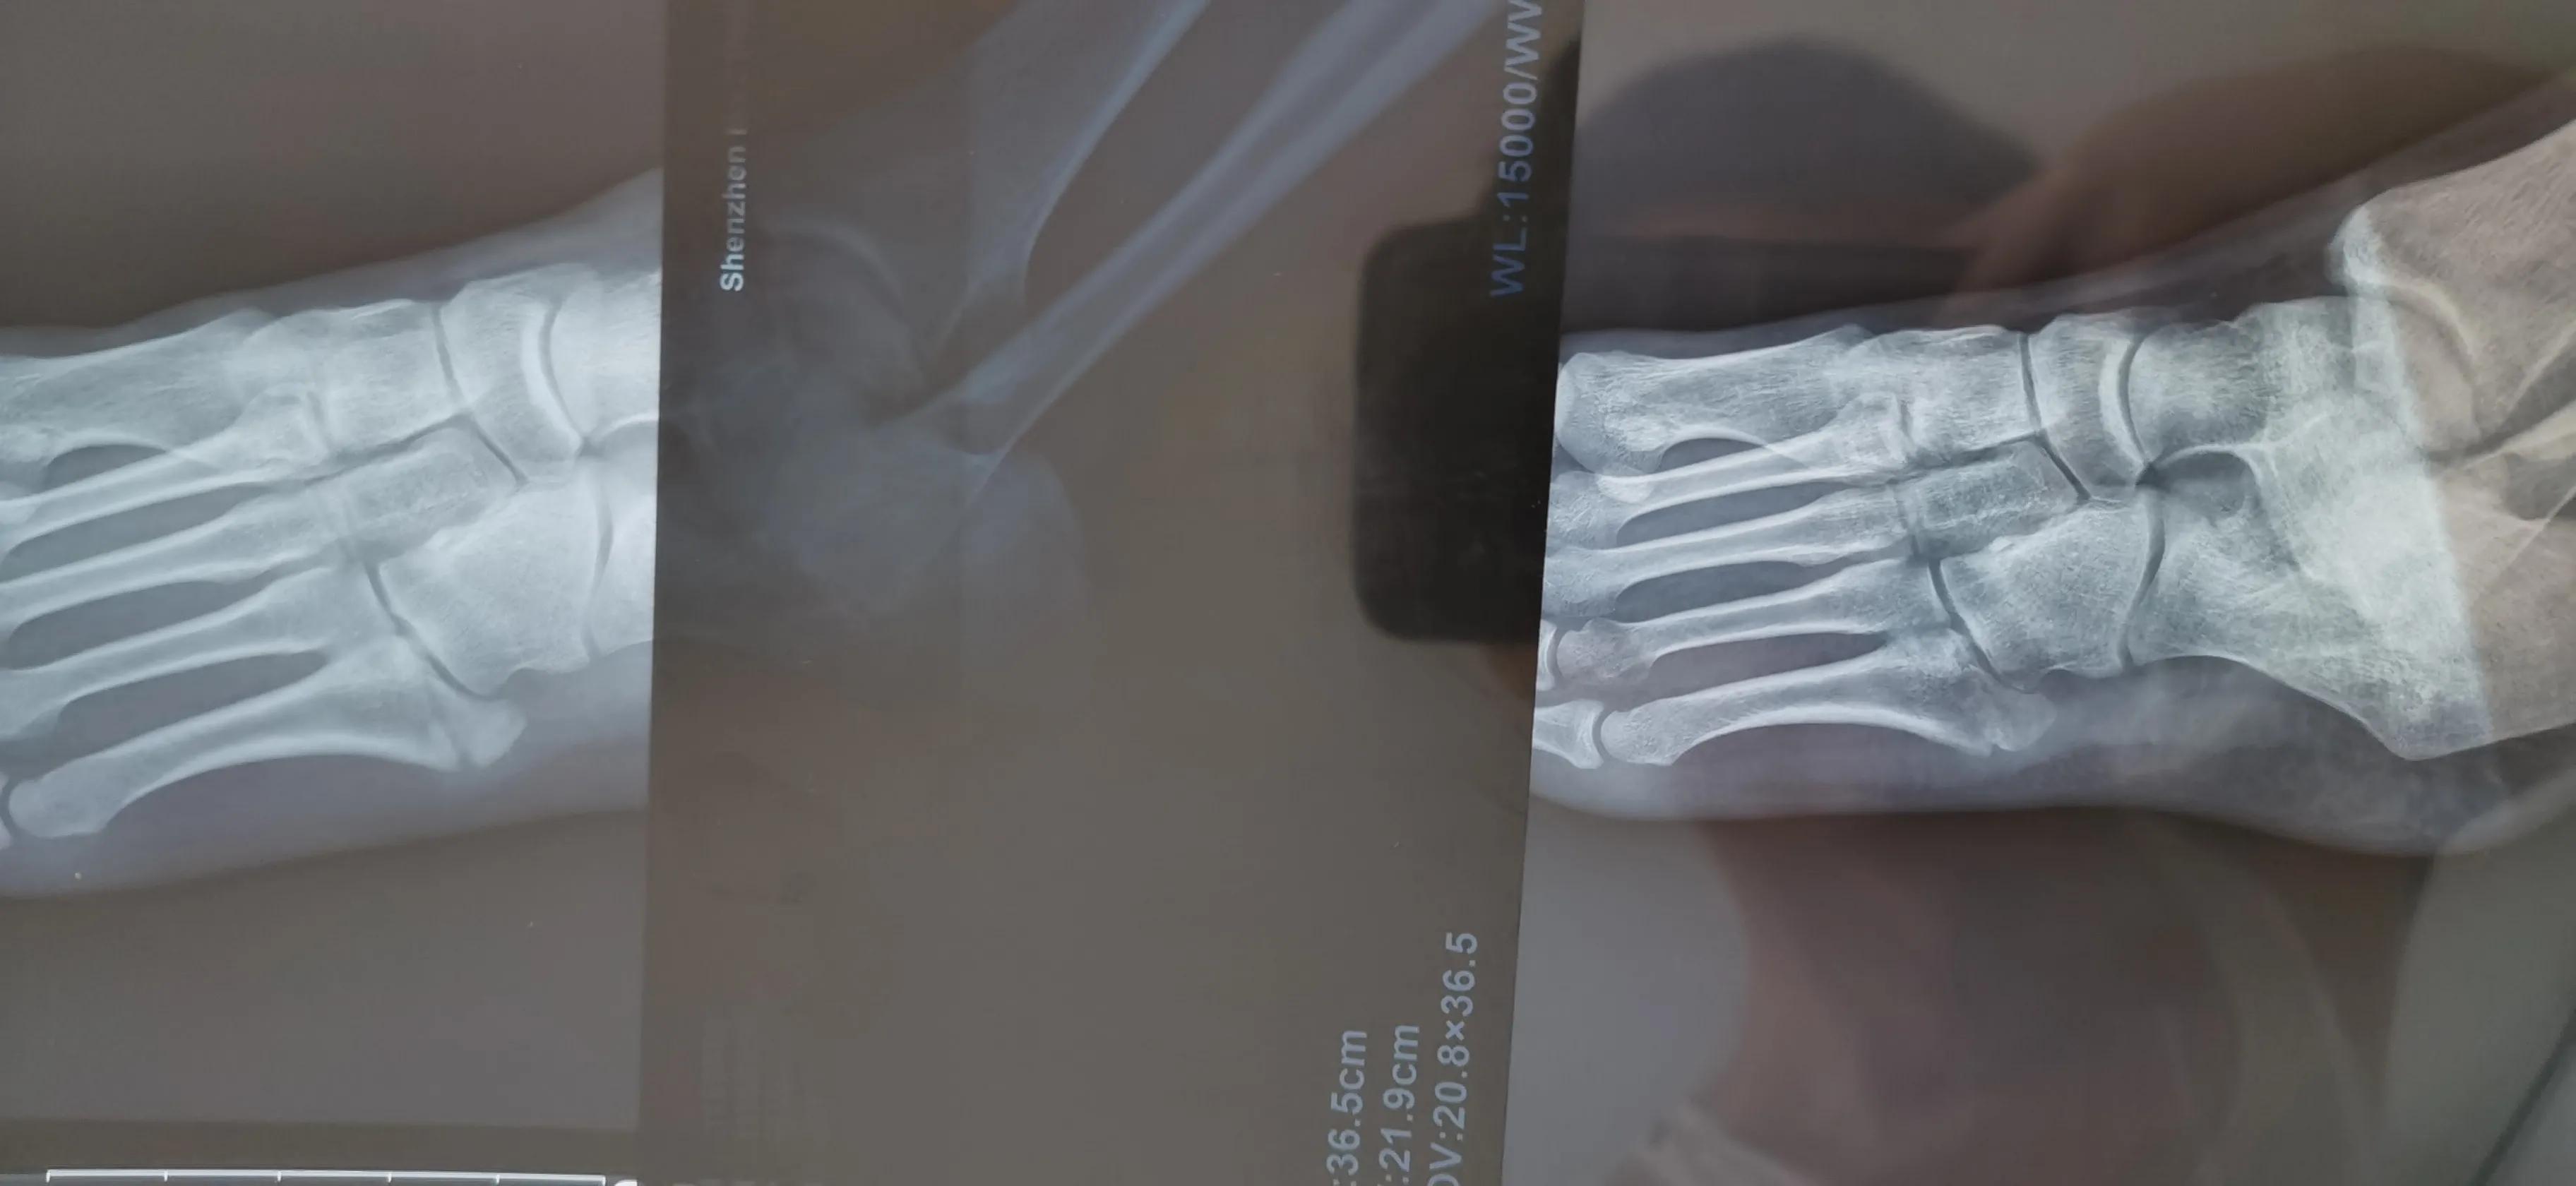

7月底拍了一个CT,愈合不明显,原来第四跖骨也有骨裂,之前都没发现,所以一定要去好医院,好医院器材好,医生经验丰富诊断准确水平高,态度也很有耐心很负责

对比6月和8月